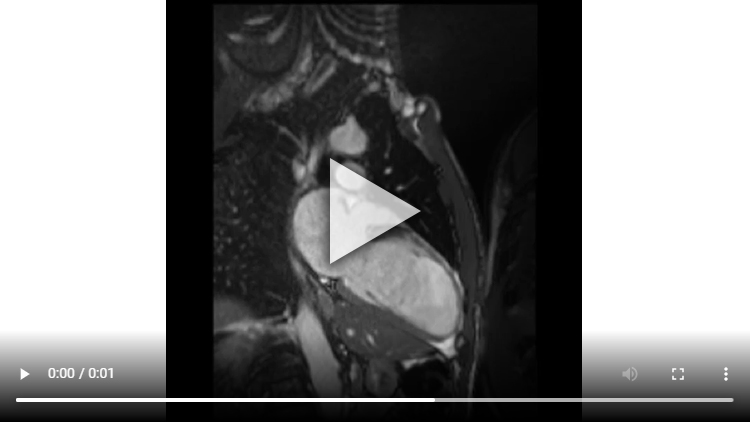

Figure 1B : Séquence Ciné-IRM - Coupe 2 cavités

Présence d’un VG dilaté avec VTD VG mesuré à 119 ml/m2 associé à une large hypokinésie sévère, voire akinésie dans certains segments, de toute la paroi antéro-septo-apicale et débordant sur la paroi apico-latérale.

Altération de la FEVG mesurée à 33% après segmentation VG.

Aucun thrombus intra-VG n’est visualisé sur ces séquences de ciné-IRM.